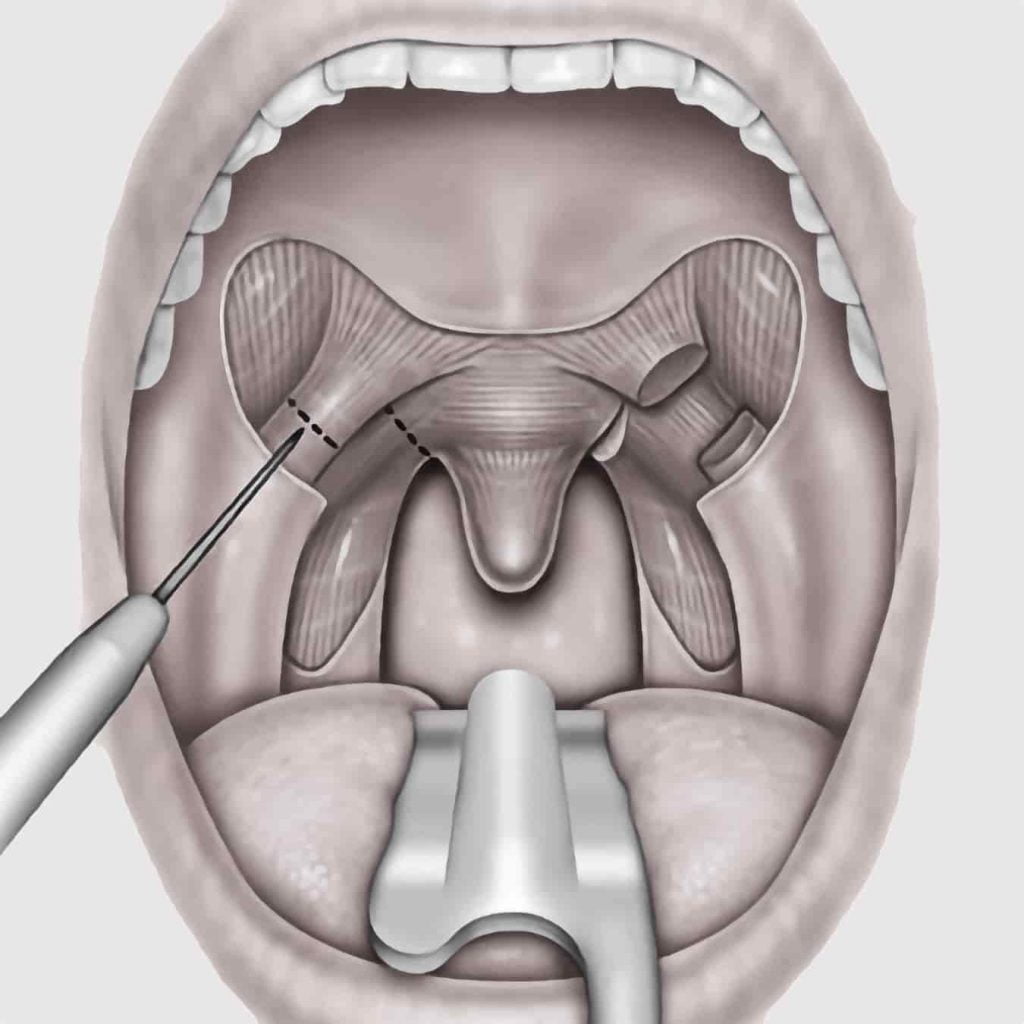

FESS & Septoplasty

April 2023